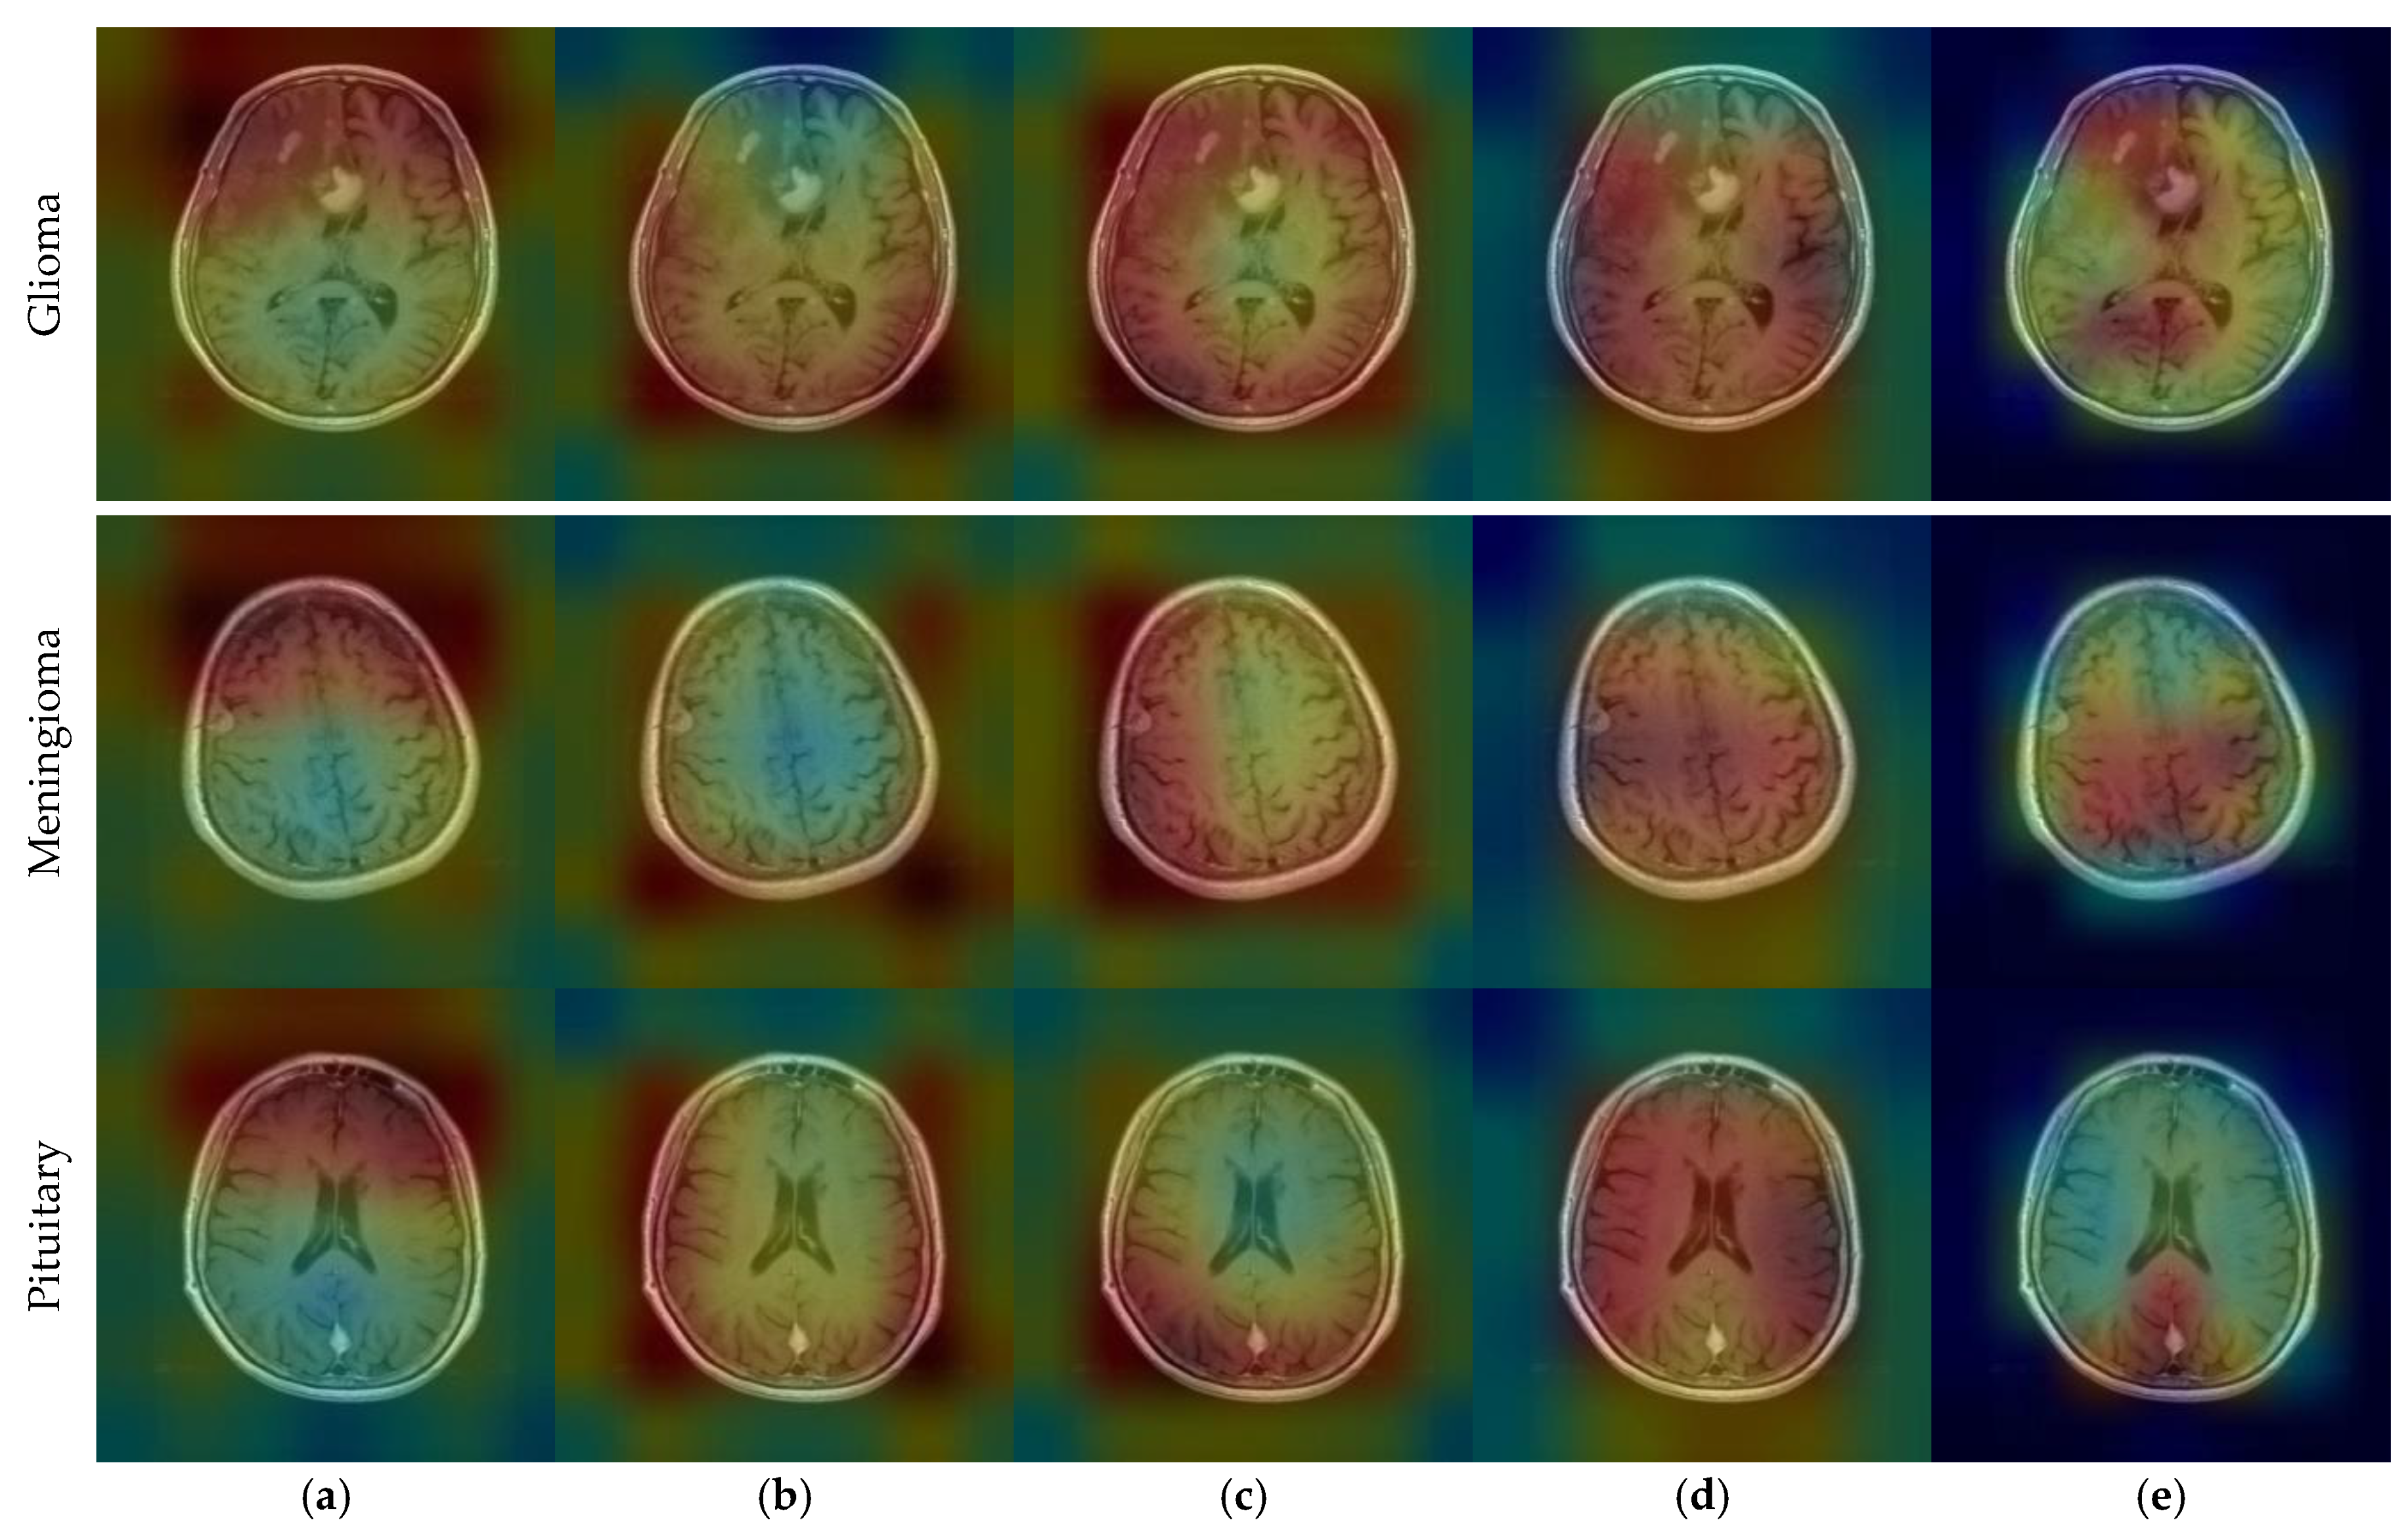

CNN outputs visualized on a heat map with Grad-CAM for Dataset 1, Dataset 2, and Dataset 3 are represented in Figure 10, Figure 11 and Figure 12, respectively. The original images are overlaid with a color spectrum ranging from blue to red, where the red regions indicate the dominant focus during model predictions. The sample images in Figure 1 were used as the original images in the Grad-CAM application. Grad-CAM analyses of the models in the ensemble framework are presented for three data sets. Figure 10 shows that while all models focus on the brain, different models may focus on different regions of the same MRI image. This trend also helps to increase feature diversity. This can be considered an indicator of better performance with ensemble learning.

Figure 11.

CNN outputs visualized on a heat map with Grad-CAM for Dataset 2: (a) DenseNet121, (b) DenseNet169, (c) DenseNet201, (d) InceptionResNetV2, and (e) ResNetRS100.